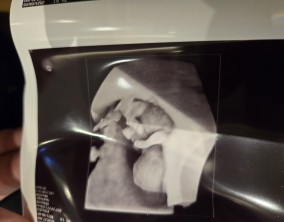

기대하지 않았던 두 줄, 그리고 끝까지 이어진 믿음

이경훈 원장님이 아니었다면 소중한 아기를 품을 수 없었을 것이라 생각합니다. 자궁 후굴이 심한 제 상황을 고려해 여러 방법을 연구하고 시도해 주신 덕분에 지금의 결과를 만날…